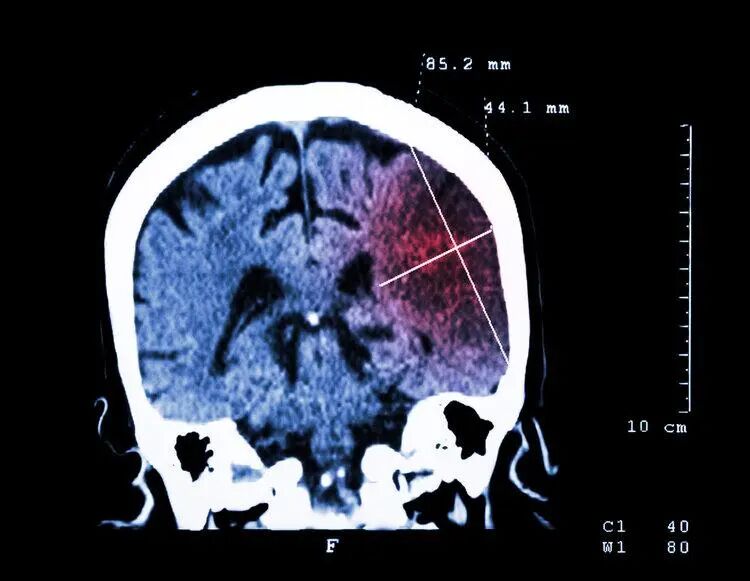

医生检查后说,老李是轻微脑梗,幸好送得及时,不然后果不堪设想。

老李躺在病床上,心里那个后怕啊,他想:“难道70岁真的是个坎儿?我怎么就这么倒下了呢?”